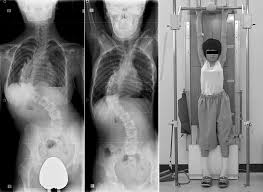

اختبار التعليق المحوري هو وسيلة آمنة وبسيطة لتحديد مدى مرونة العمود الفقري. في هذا الفحص، يُرفع جسم المريض بلطف من الرأس أو الرقبة باستخدام جهاز خاص، مما يخفف الضغط عن العمود الفقري ويُظهر مدى قابليته للاستقامة.

خلال الفحص، يلتقط الطبيب صور أشعة من الأمام والجانب ليقارن شكل العمود الفقري أثناء التعليق مع وضعه الطبيعي. بهذه الطريقة، يعرف الطبيب مدى استجابة العمود الفقري للتصحيح قبل الجراحة.

يُجرى الاختبار في مركز أشعة مجهز. يقف المريض في وضع مريح، ثم يُرفع الرأس بلطف بجهاز مخصص. لا يشعر المريض بأي ألم أو ضغط.

خلال الاختبار تُلتقط صورتان بالأشعة:

الأولى من الأمام لتقييم الاستقامة.

الثانية من الجانب لمراقبة الانحناءات الطبيعية.